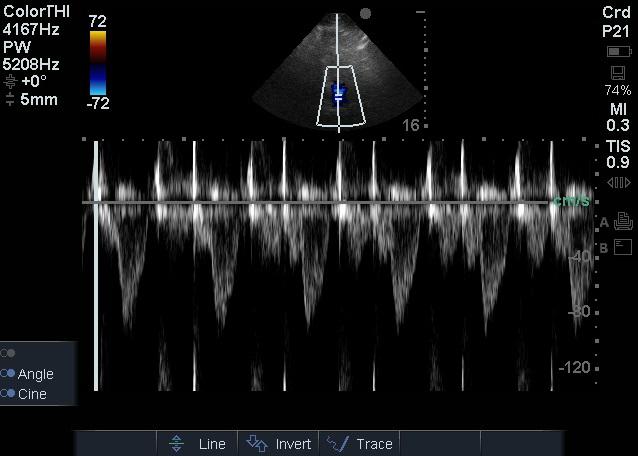

1.2 方法患者入院24 h内完成心脏超声检查。患者左侧卧位,以能显示心尖四腔心切面及五腔心切面为准,以美国Sonosite公司Edge超声诊断系统相控阵探头经心尖对患者二尖瓣、LVOT进行评估,彩色多普勒显示血流束,脉冲型频谱多普勒测量二尖瓣E峰流速及LVOT峰值流速(图 1~2),连续显示多个呼吸周期,选取呼吸周期内血流速变化规律波形,测量血流速最大值及最小值,重复以上过程,每个测量部位血流速共测量三组最大值及最小值,然后计算平均数。二尖瓣E峰流速呼吸变异度=(二尖瓣E峰流速最大值-二尖瓣E峰流速最小值)/[(二尖瓣E峰流速最大值+二尖瓣E峰流速最小值)/2],LVOT峰值流速呼吸变异度=(LVOT峰值流速最大值-LVOT峰值流速最小值)/[(LVOT峰值流速最大值+LVOT峰值流速最小值)/2][1]。

| 图 2 二尖瓣频谱多普勒检查 Figure 2 Mitral valve spectral Doppler examination |

作为心内尤其是左心血流,二尖瓣血流自二尖瓣开放开始持续整个舒张期,在超声频谱多普勒图显示为双峰,第一峰(E峰)为舒张早期心室主动舒张血流充盈左心室所致,第二峰(A峰)为舒张末期心房收缩形成的加速血流,此时心室被动充盈,在舒张期末左心室达到最大容积,随后左心室收缩,血流经左室流出道射入主动脉。作为左心入口及出口的血流,脓毒症患者二尖瓣E峰流速与LVOT峰值流速均数比较差异无统计学意义,提示在LVOT峰值流速难以测量时,参考二尖瓣E峰流速可能有意义;二尖瓣E峰流速呼吸变异度大于LVOT峰值流速呼吸变异度,差异有统计学意义(P < 0.01),提示不能简单地以二尖瓣E峰流速呼吸变异度代替LVOT峰值流速呼吸变异度。